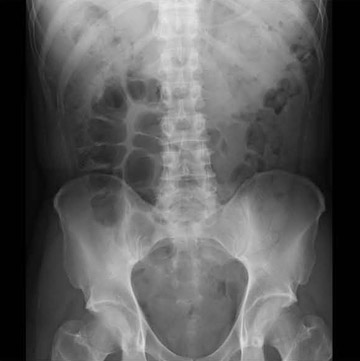

1.大視野,高精細,高濃度階調

検出器サイズ43cm×43cm,画素ピッチ148μmの高感度,高精細のX線検出器で,連続透視とパルス透視,および最大15fpsまでの撮影が可能である。視野サイズが広くなったことで,泌尿器検査においてはFPDによる腎尿管膀胱単純撮影(KUB)と腎盂造影が可能となり,透視検査後のカセッテ撮影の準備を行う必要がないため,検査効率が向上する。また,従来のFPDシステムの画像は,濃度階調10〜12ビットで出力および保存していたが,FPD1717では,16ビットのままHDD保存とDICOM保存を行う。これにより,画質を劣化させることなく高度な画像処理を行うことを可能にする。ユーザがウインドウ調整を実施する場合も滑らかな階調が維持されるため,画像処理の自由度が高い。腹部単純撮影で,腸閉塞,腎結石,尿管結石などの急性腹症を診断する場合に,腸管ガス,腎臓,肝臓,脾臓,大腰筋,横隔膜など,目的部位に合わせた階調処理を行うことで診断情報が増加する(図3)。

図3 FPD1717による腹部単純撮影像 |